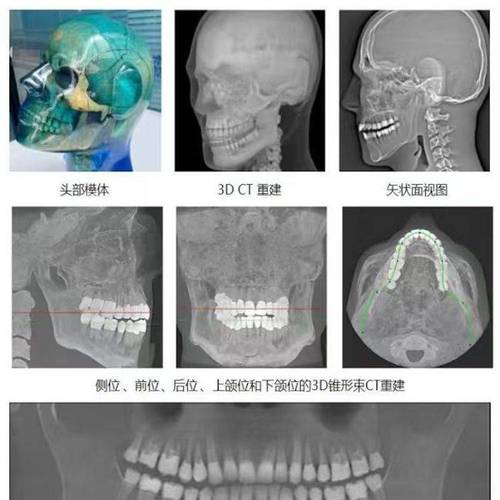

牙齿矫正头颅侧位片是口腔正畸诊断中不可或缺的影像学检查,通过拍摄头颅侧面的X线影像,全面评估颅颌面骨骼、牙齿及软组织的形态与位置关系,为矫正方案设计提供精准的解剖学依据,其核心价值在于将复杂的颌面结构转化为可量化、可分析的数据,帮助正畸医生判断错颌畸形的类型、机制及严重程度,从而制定个性化的治疗策略。

头颅侧位片贯穿矫正全程,是诊断、设计、评估的核心工具,通过量化骨骼与牙齿关系,明确错颌类型(如骨性II类、III类、垂直生长型等),区分“骨性问题”与“牙性问题”,避免盲目矫正,骨性III类患者(ANB<0°)需结合生长发育潜力判断是否需要正畸-正颌联合治疗,而非单纯牙齿移动,在方案设计阶段,通过预测牙齿移动对骨骼及软组织的影响(如拔牙后前牙内收量对侧貌的改善),制定拔牙与否、支抗类型(如微种植支抗)等关键决策,矫正过程中定期拍摄头颅侧位片,可动态评估牙齿移动是否符合预期(如切牙倾斜度变化、磨牙关系调整),及时调整方案;治疗后通过对比分析,验证矫正效果(如覆颌覆盖正常、侧貌协调)及长期稳定性。

头颅侧位片的准确性依赖于拍摄标准化,任何头部倾斜、旋转均会导致测量误差,需由专业技师操作,对于生长发育期儿童,需结合手腕骨龄片评估生长潜力,头颅侧位片可定期拍摄(如每6-12个月)以监测骨骼变化,头颅侧位片需与全景片(观察牙根、牙槽骨)、口腔模型(分析牙弓形态)等联合应用,实现多维度评估,避免单一检查的局限性。